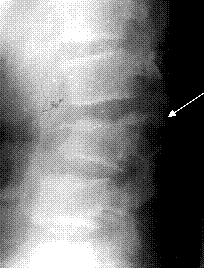

Признаками сгибательно-дистракционного повреждения является увеличение расстояния между соседними остистыми отростками на прямой и боковой рентгенограмме (рис. 3А) и локальный кифоз (рис. 3Б).

|

| А |

Б |

| Рис. 3. Рентгенологические признаки сгибательно-дистракционного повреждения |